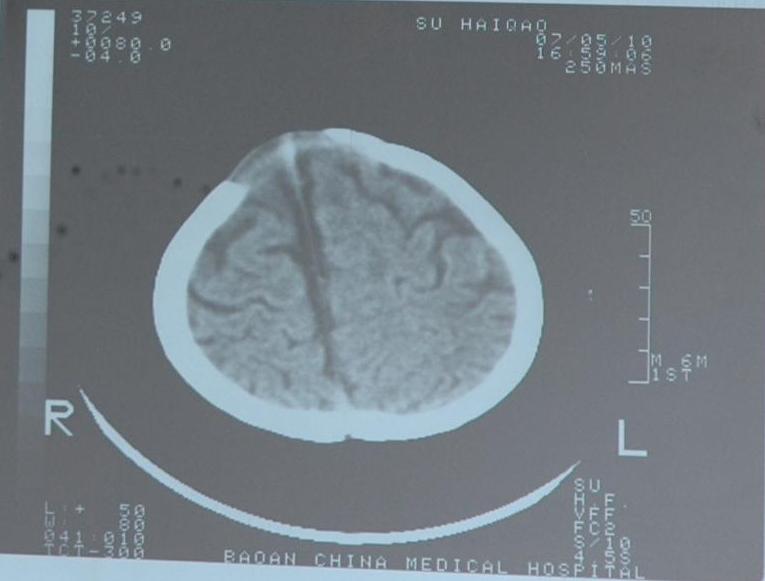

检查部位:头颅ct扫描

层厚:10mm     层距:10mm

扫描所见:双侧额颞部颅骨内板下方见对称性带状脑脊液样低密度影,并向前纵裂延伸,两侧大脑半球、脑干及小脑实质密度未见异常,侧脑室及三脑室略宽,双侧额叶脑沟深深加宽。四脑室形态无变形、移位或扩张,中线结构居中。

ct诊断:1、外部性脑积水(少量)。2、侧脑室、三脑室略宽,双侧额叶脑沟增深加宽,请结合临床。